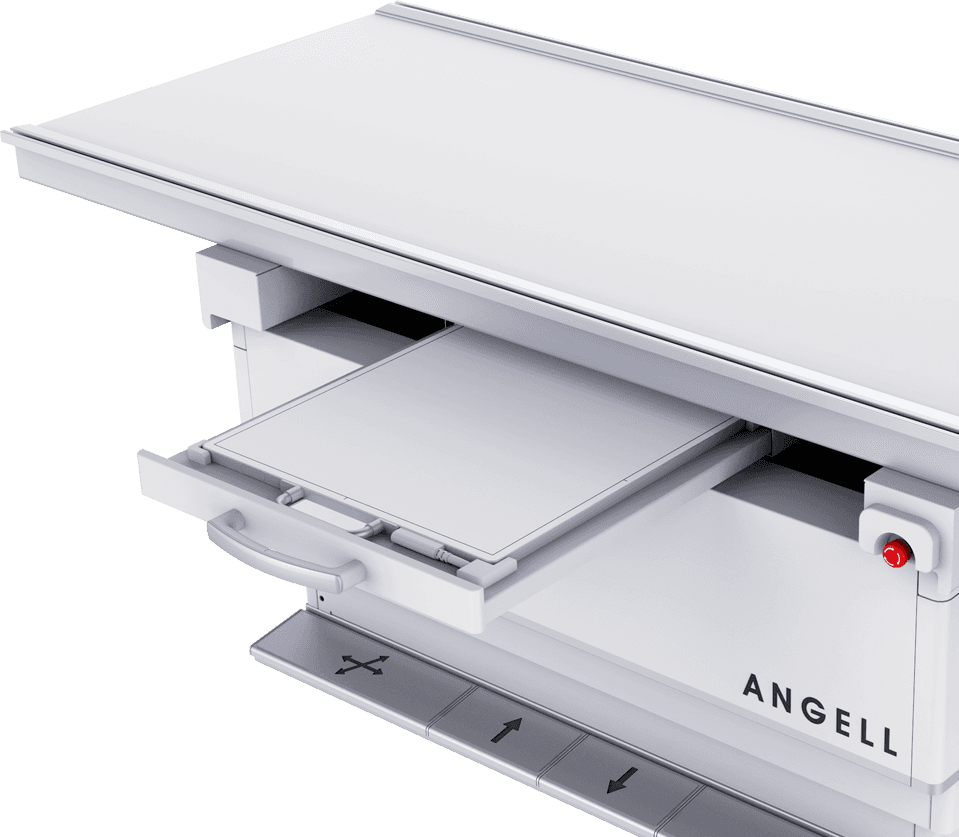

¶ЇѕІЛ«°еЧФУЙЗР»»

¶ЇМ¬ЖЅ°е+ѕІМ¬ЖЅ°еЛ«°еЕдЦГЈ¬їЙКµПЦєБГлј¶СЎ°еЗР»»ЎЈ

ЕдєПКЦЧФТ»МеРьµхКЅ»ъРµФЛ¶ЇПµНіЈ¬¶аМеО»ЕДЙгЧЄ»»ЗбЛЙЧФИзЈ¬ґу·щМбЙэБЩґІјмІйР§ВК -

µНМеО»Бй»оЕДЙг

МЅІвЖчєНЗт№ЬїЙЅµЦБЅфМщµШГжЈ¬НкіЙПВЦ«¶аЅЗ¶ИЙгУ°Ј¬

јхЙЩІЎИЛТЖ¶ЇЈ¬Н¬К±±гУЪ¶щНЇБўО»ЎўЛДЦ«ЕДЖ¬ЎЈ -